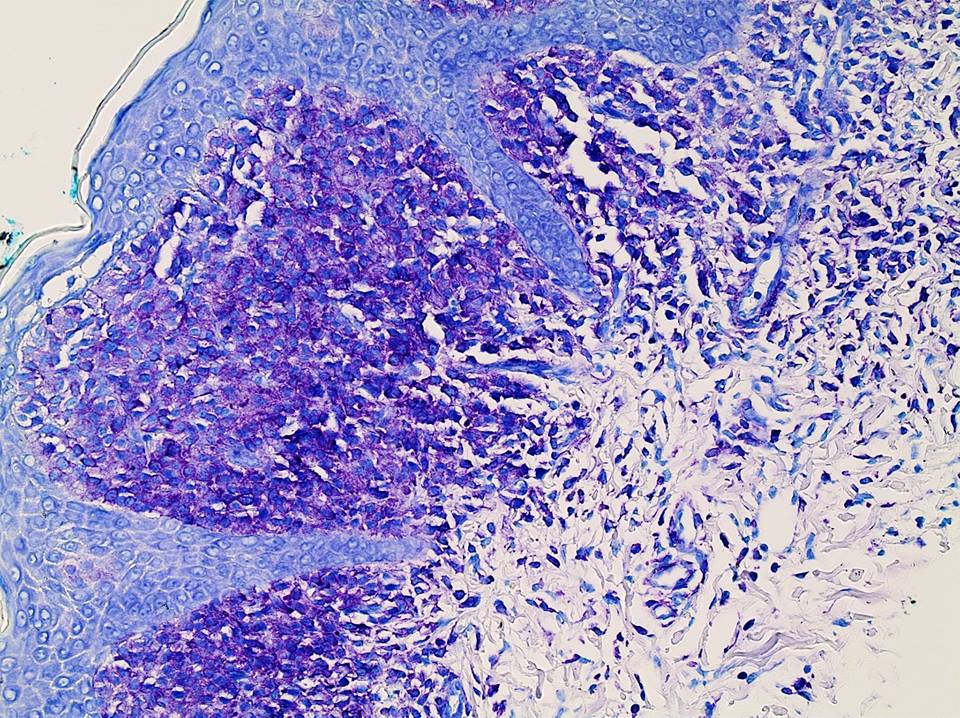

Positive stains

- Toluidine blue and Giemsa demonstrate metachromasia (granules are purple red)

- Leder (chloroacetate esterase), CD117 / c-kit

Microscopic (histologic) images